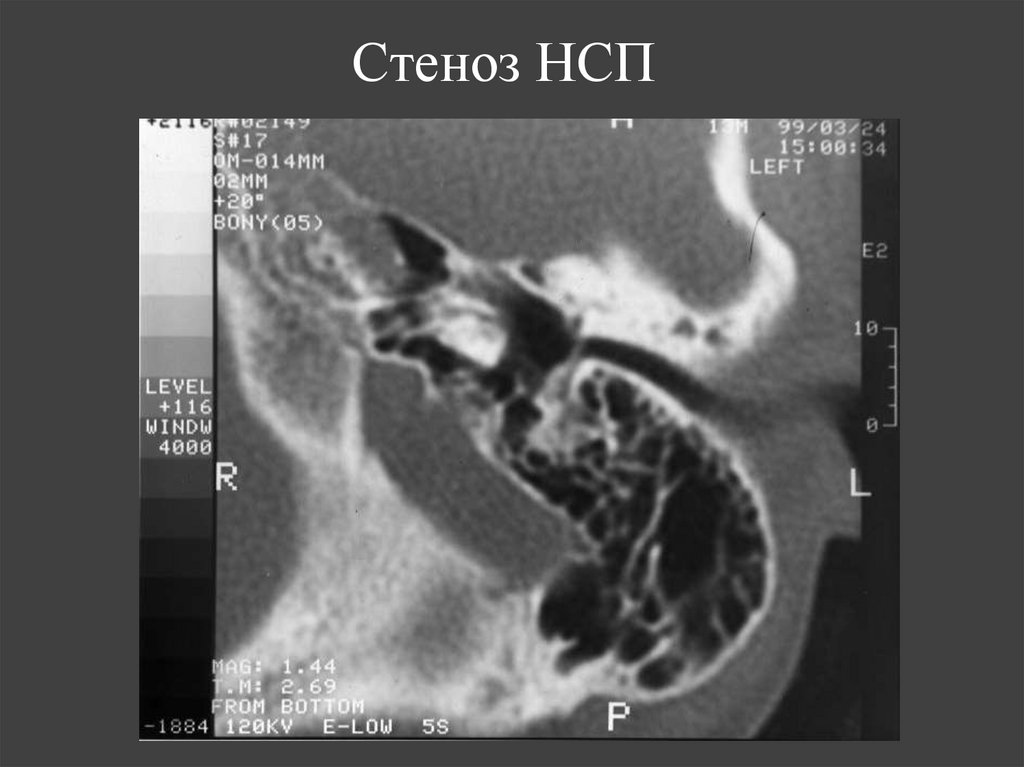

153. Стеноз НСП

20.

Стеноз наружного слухового прохода

Стеноз НСП